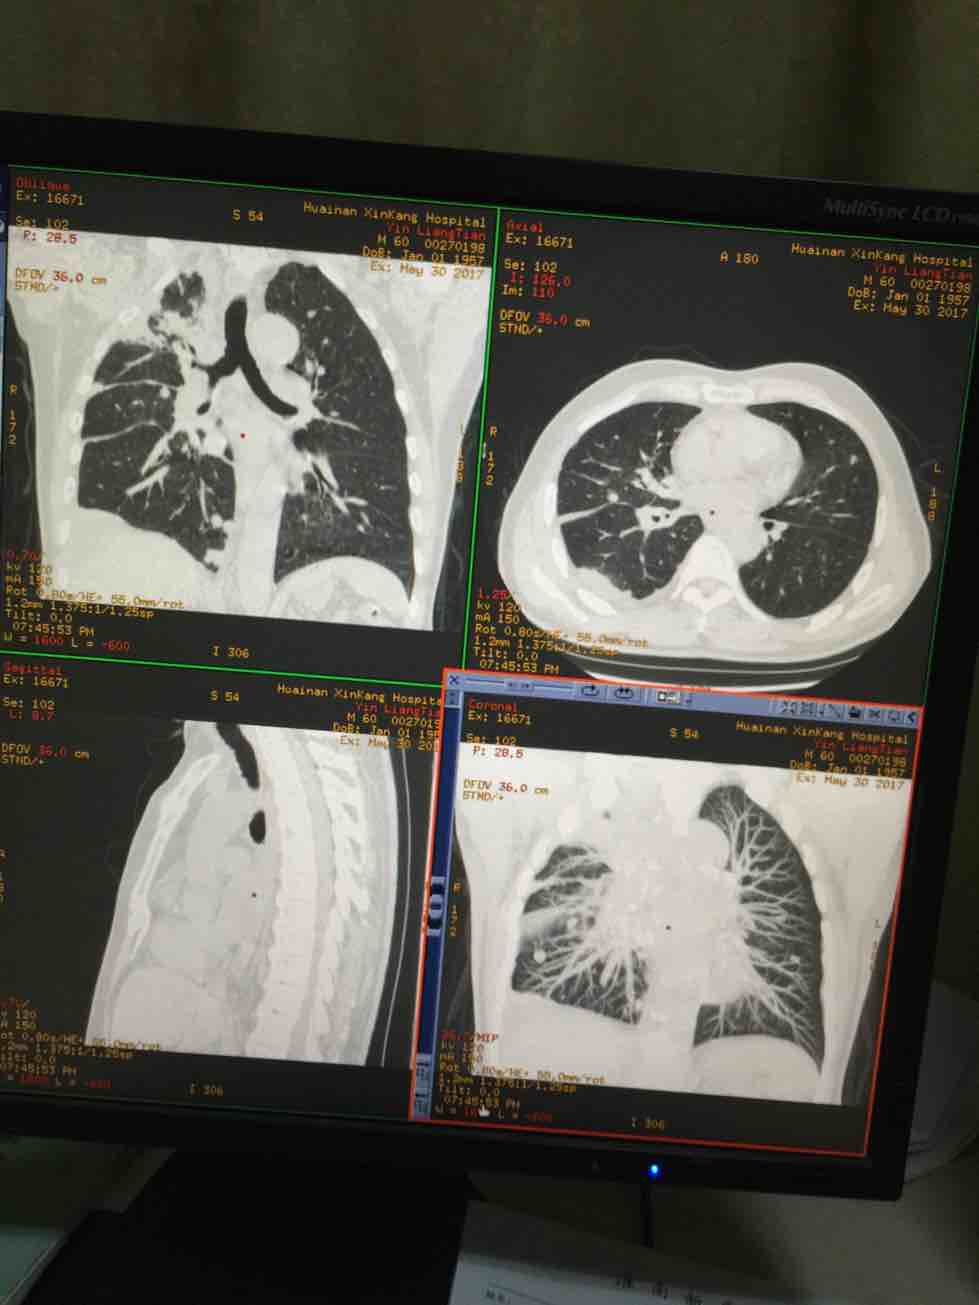

我父亲2016年一月发现右上肺癌晚期,培美曲塞六个疗程后行了右上肺原发灶两周放疗,于去年7月份进展,后来基因检测没有突变,盲吃印版易瑞沙后结果有效,瘤子很快缩小,至今吃了第八盒,最近说胸痛今日CT复查(结果如图)进展了,接下来如何治疗还请各位老师给予指导,谢谢!!